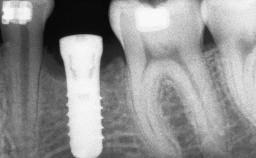

| # of Implants | 8 |

| Type of Implants | Reduced-Diameter|Two-Piece |

| Bone Augmentation | Horizontal|Sinus Floor Elevation|Staged|Vertical |

| Augmentation Materials | Autogenous chips|Autogenous block(s) |

| Bone Volume | Deficient vertically or deficient vertically AND horizontally |